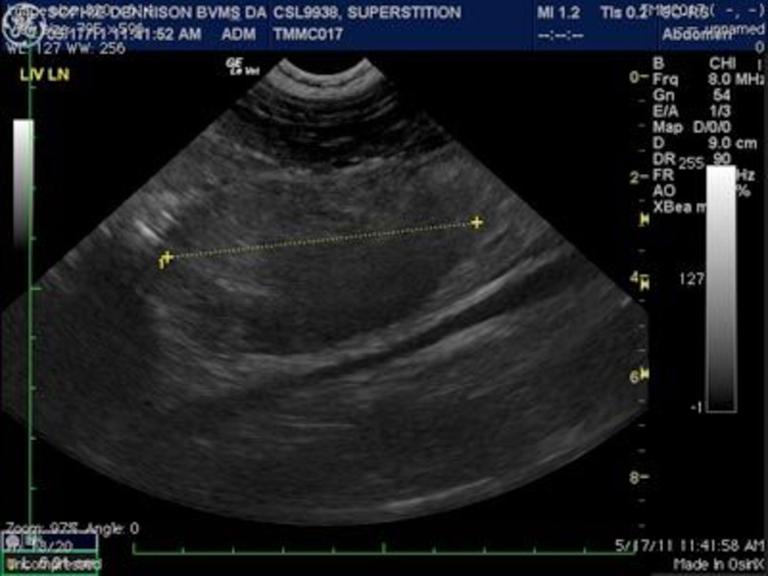

海洋哺乳動物中心為一隻加州海獅照超音波,測量腹部腫瘤。這隻暱稱為「迷信」的海獅死於癌症。PHOTOGRAPH BY THE MARINE MAMMAL CENTER